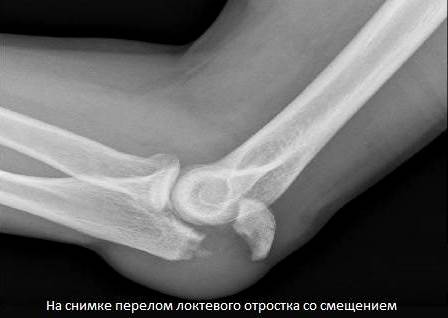

При таких травмах обычно повреждения локализованы в верхних третях локтевых костей. Происходит перелом локтевого отростка (переломо-вывихи Монтеджи).

Если произошло спровоцированное тягой трицепса смещение фрагмента, то проводится только оперативное лечение. Хирург восстанавливает хрящевые и костные ткани, а затем фиксирует отломки спицами и проволокой. Удаляют спицы примерно через полгода после оценки состояния локтя. А пластины извлекаются позже — через 1-2 года.

Благодаря близкому расположению локтевого отростка к коже операция длится недолго и не представляет сложности. Но есть и исключения — многооскольчатые переломы с повреждениями венечных отростков. Они закрепляются специальными хирургическими металлическими конструкциями.